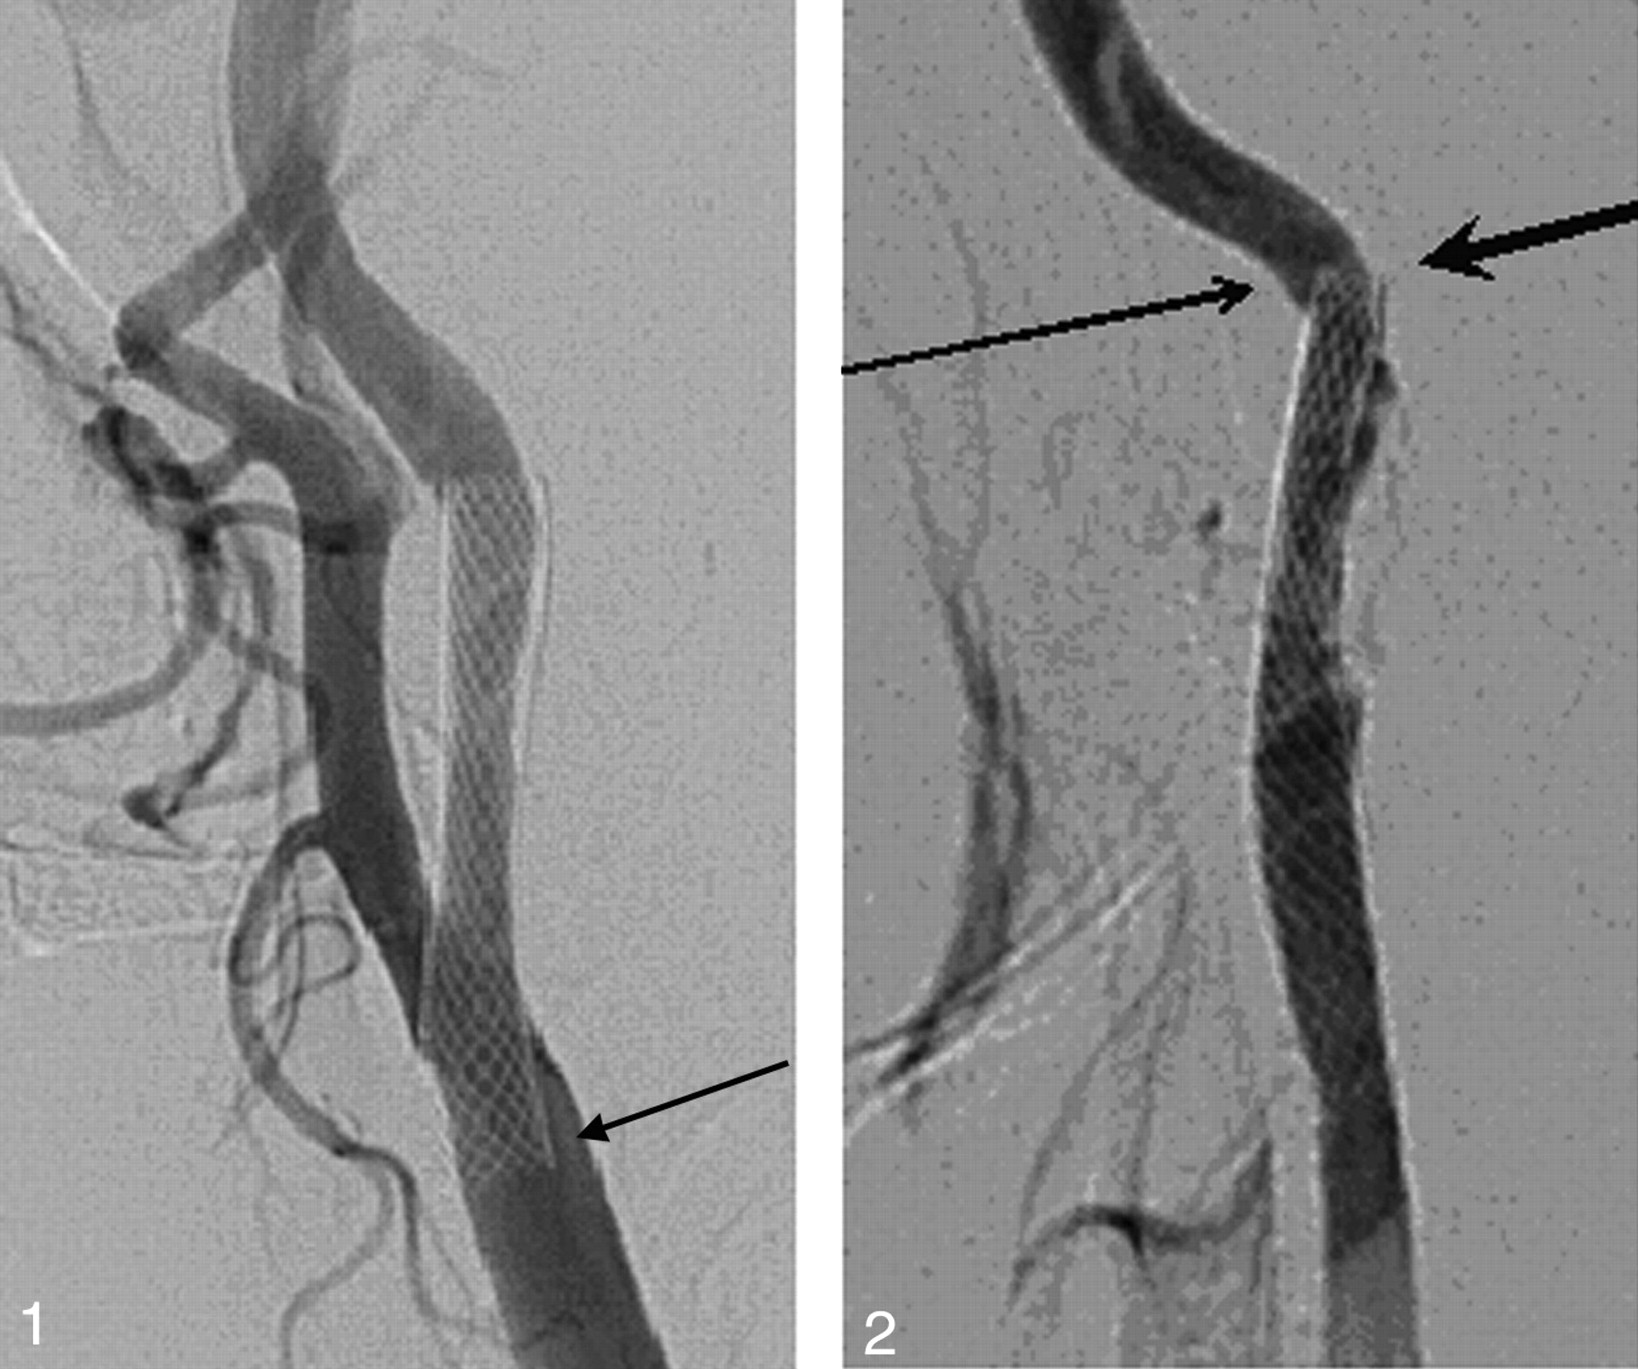

Patient 9. A 60-year-old man with transient ischemic attacks. A left carotid angiogram revealing an incomplete stent apposition at the distal stent edge (small arrow) and stent-induced kinking (large arrowhead).